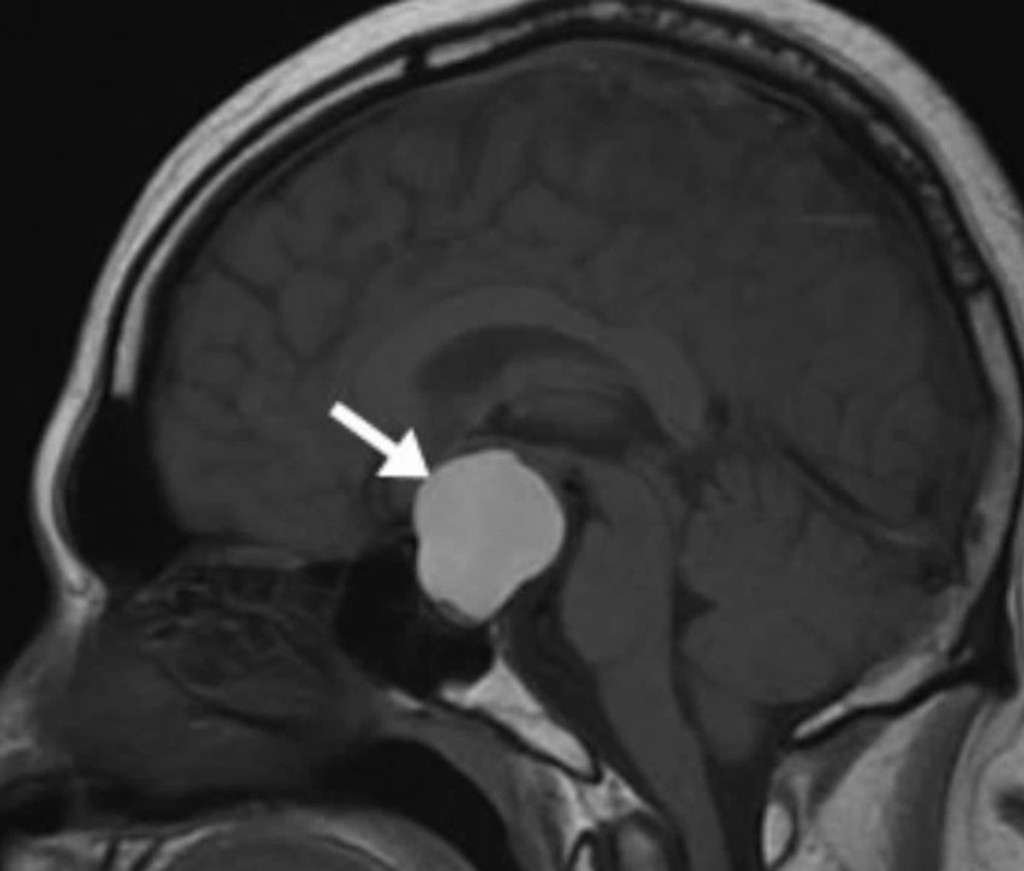

Zuby v nádore sú niečím veľmi jedinečným a ojedinelým. Lekári v Marylande diagnostikovali malému len štvormesačnému chlapčekovi rakovinu. Nádor v jeho mozgu mal 4,1 cm x 4 cm x 3,5 cm. Zistili to vďaka testom, ktoré preukázali, že bábätku sa hlava zväčšuje príliš rýchlo.

Chlapčeka operovali a v nádore našli niečo veľmi vzácne. Vyrastali z neho zuby. „Zuby v akomkoľvek druhu nádoru v mozgu teda nevidíme každý deň. A v kraniofaryngióme už vôbec," povedal neurochirurg Narlin Beaty, ktorý operoval. Podľa Metro.co.uk je už chlapček v poriadku a je zdravý.